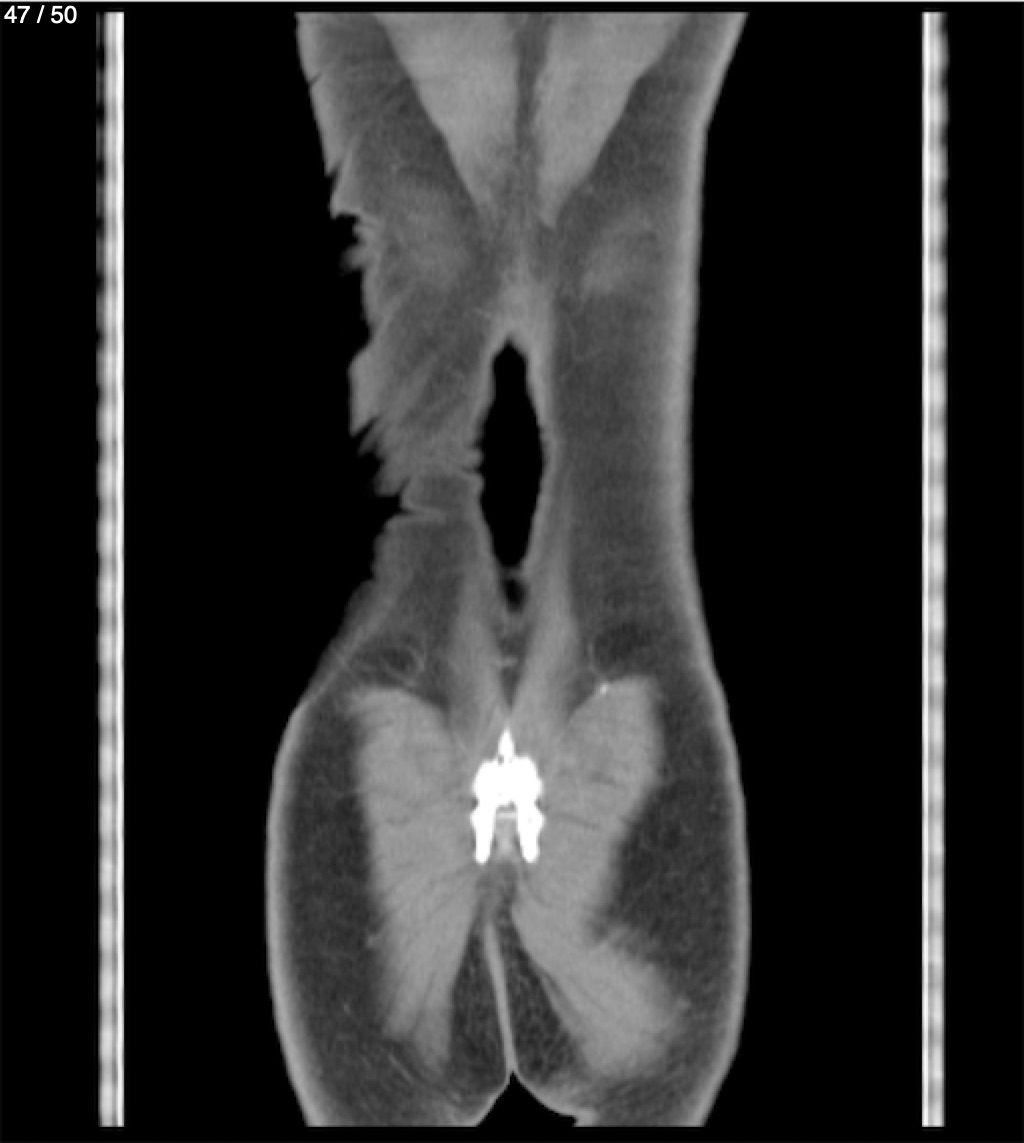

Alonso Victorio Ruiz 62A - T.C Abdomen Syc